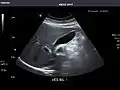

Abdominal Ultrasound (Full Exam)

STRUCTURED REPORT

(Technique: Transabdominal ultrasonography; Device: Toshiba Aplio XG)

Liver: Diffusely homogeneous and normal in echogenicity. No focal mass or contour nodularity. No intrahepatic biliary ductal dilatation.

Portal Vein: Patent main portal vein.

Gallbladder: No stones, wall thickening, or pericholecystic fluid.

Common Bile Duct: Nondilated measuring 1.3 mm at the level of the porta hepatis.

Pancreas: Visualized portions unremarkable.

Spleen: Normal in size.

Kidneys: Right and left kidneys measure 11.5 cm and 12 cm in length respectively. No hydronephrosis. Small left lower pole kidney cyst.

Ascites: None.

Aorta: Visualized portions normal in caliber, 16 x 15 mm.

IVC: Normal.

IMPRESSION:

Normal abdominal ultrasound.